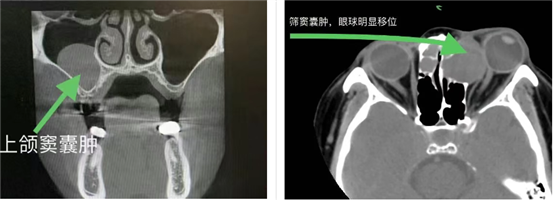

5.眼部症状:若囊肿位于眼眶附近,可能引起眼球突出、视物重影、视力下降等表现。

3.影像学检查:如X线、CT或MRI,有助于了解鼻窦结构及囊肿的位置、大小与范围。